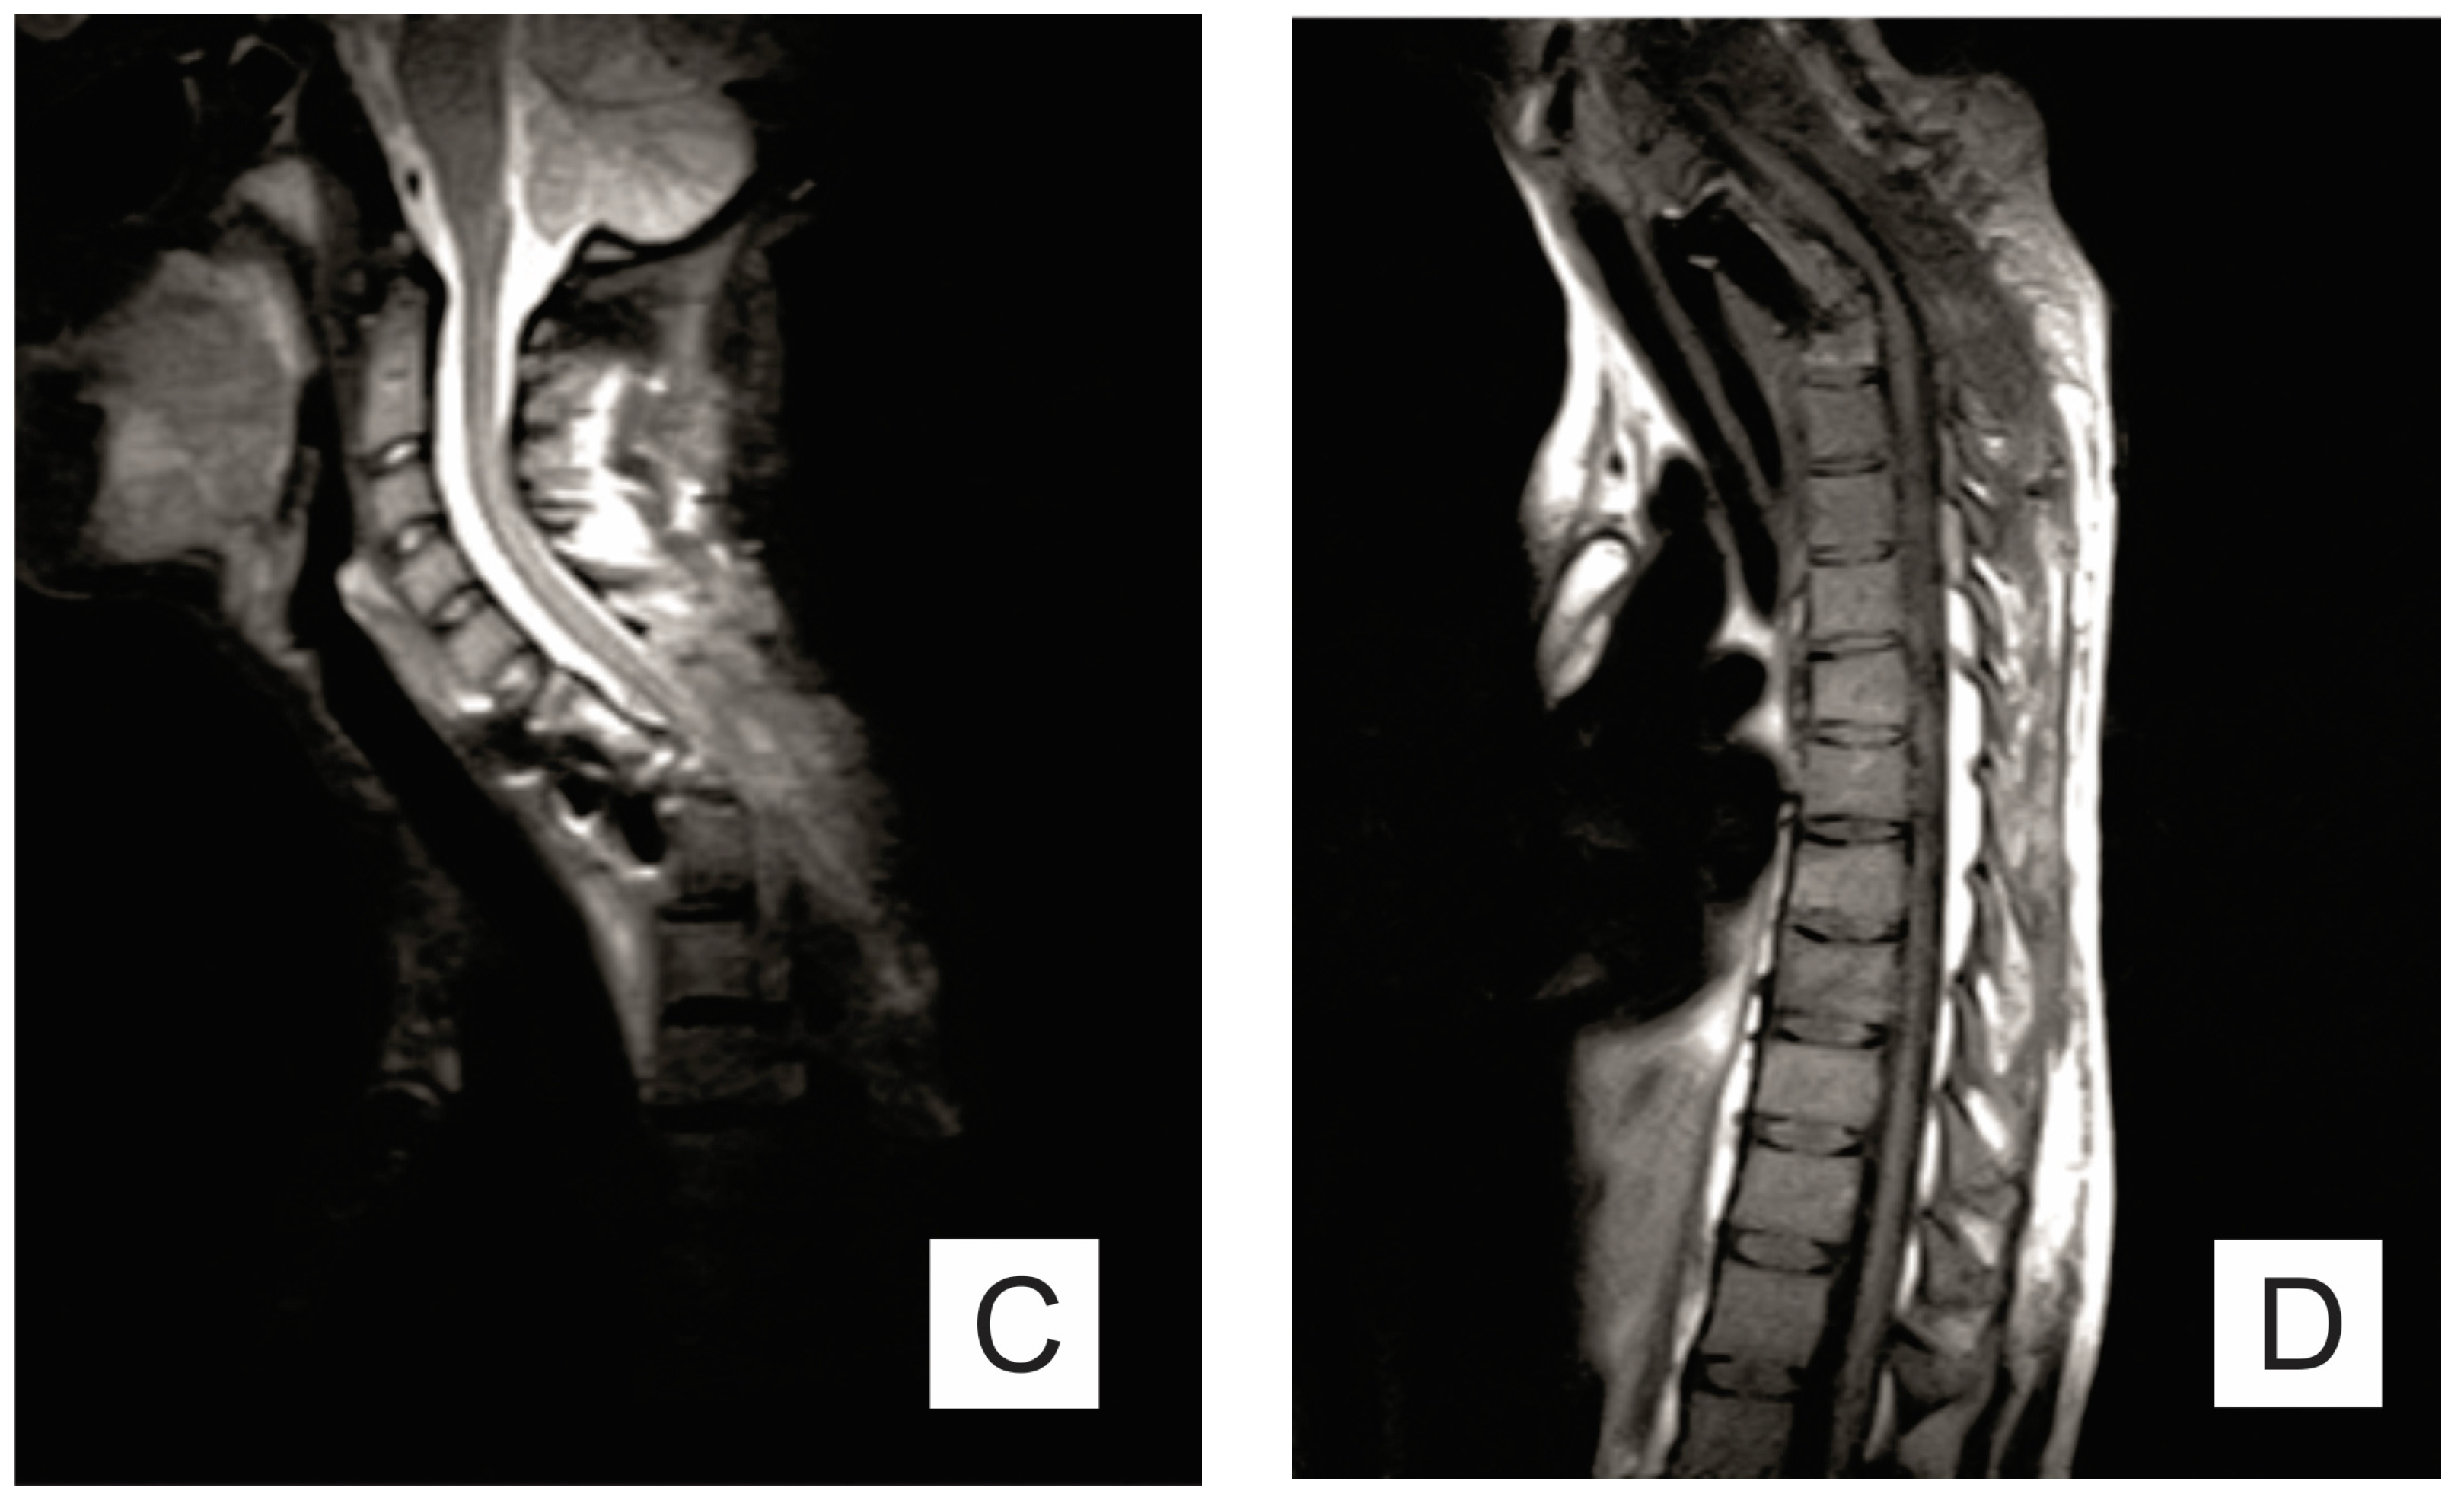

2. Case Report